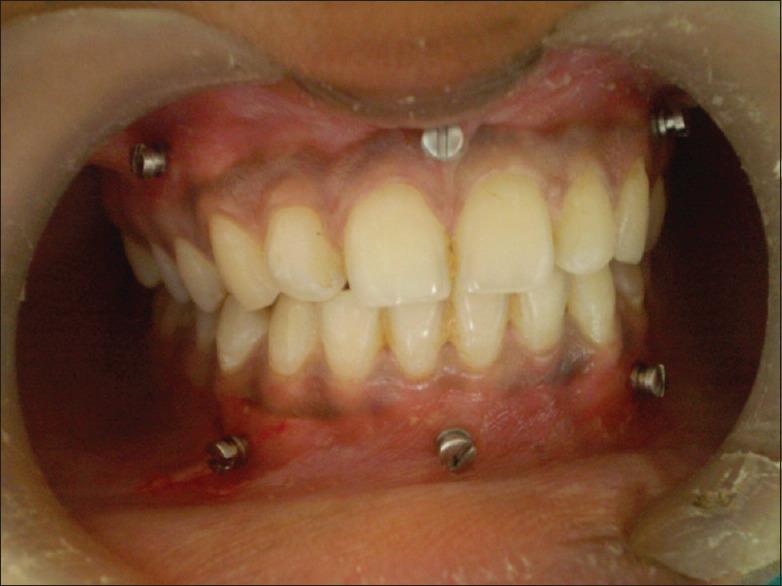

MATERIALS AND METHODS

Sixty dentulous patients who reported to Department of Oral and Maxillofacial Surgery, Al-Ameen Dental College and Hospital, Bijapur with mandibular fractures and required intermaxillary fixation as a part of treatment plan followd by open reduction and internal fixation under GA were selected and randomly divided into 2 groups of 30 patients each that is Group A and Group B. Group A included patients who received intermaxillary fixation with Erich arch bars. Group B includes patients who received intermaxillary fixation with IMF Screws. The parameters compared in both the groups included, surgical time taken, gloves perforation, post-operative occlusion, IMF stability, oral hygiene, patient acceptance and comfort and non-vitality characteristics.

选取 60 例到比贾布尔 Al-Ameen 牙科学院和医院口腔颌面外科就诊的下颌骨骨折患者,他们需要进行颌间固定作为治疗计划的一部分,随后在全身麻醉下进行切开复位内固定。将患者随机分为两组,每组 30 例,即 A 组和 B 组。A 组患者接受 Erich 牙弓夹板颌间固定。B 组患者接受颌间固定螺钉固定。两组比较的参数包括手术时间、手套穿孔情况、术后咬合、颌间固定稳定性、口腔卫生、患者接受度与舒适度以及无活力特征。

A 组的平均手术时间和手套穿孔次数更多,B 组的患者接受度和口腔卫生状况更好,两组术后咬合和颌间固定稳定性在统计学上无显著差异。意外牙根穿孔是颌间固定螺钉的唯一局限性。

在治疗下颌骨骨折方面,与 Erich 牙弓夹板相比,颌间固定螺钉更为有效。